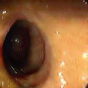

| (a) | (b) | (c) | (d) |

In this paper, we present a deep learning model for realtime visualization of missed colon surfaces directly on the colonoscopy video frames without doing any prior offline 3D reconstruction using contiguous sets of frames. Specifically, we make use of prior 3D reconstructed virtual colonoscopy (VC) [7, 8] data, created from a computed tomography (CT) scan, to produce training data for missing surface visualization (Figure 1b–d). This is used in conjunction with OC data for the same patient to drive an unpaired image-to-image translation with a modified lossy CycleGAN [4] and a new enforced shared OC and VC latent space representation. The lossy CycleGAN [4] by itself overfits due to the sparse training data for the missing surface task (most OC frames have no or few missing surface green pixels as opposed to the dense depth maps for which the lossy CycleGAN was originally proposed) and can easily hallucinate structures which do not exist, as shown in Figure 1. Adding a shared latent space forces the network to preserve structures (and avoid hallucination) when translating between domains. With added Gaussian noise, we also show that the same framework with shared latent space representations can be used to generate realistic one-to-many mappings from VC to OC and OC to OC for augmenting OC datasets in computer-aided detection and classification pipelines.

In order to create training data for per-frame missing surface visualization, the opacity of the 3D colon mesh is lowered such that the more opaque regions indicate the missed surfaces, which are colored green in Figure 1c. The per-frame missing surface data is generated through Blender and example videos are provided111Supplementary Video: https://youtu.be/x1-wwCiYeC0. Figure 1 shows a typical colon anatomy along with the haustral folds and the pictorial representation of a missed surface for a certain endoscope camera position. To aid the model with the image-to-image domain translation task, we added the missing surface information in green channel on top of the VC rendering of the colon (Figure 1d).